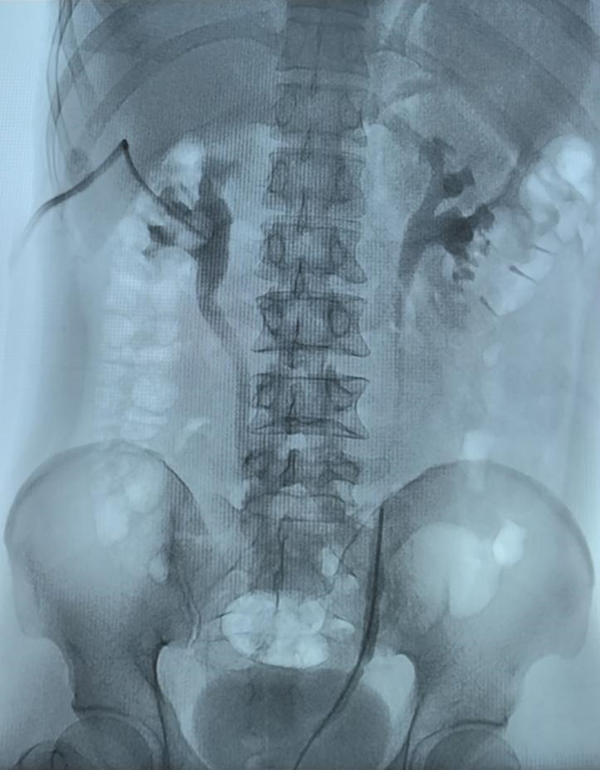

房先生术前损伤造影